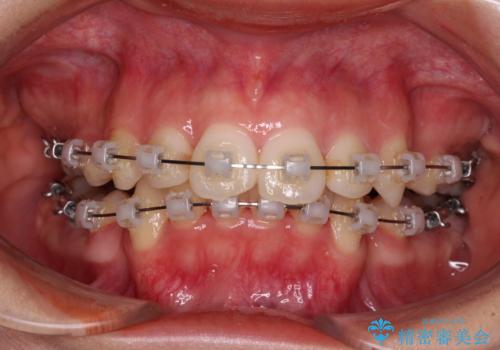

補助装置を用いて奥歯の咬み合わせを改善しながら歯列を後方に移動させ、上下左右第一小臼歯を4本抜歯することで八重歯や口元の突出感を改善することとしました。

奥歯の咬み合わせの不正が顕著であったため、表側のワイヤー装置を選択して矯正治療を行うこととしました。